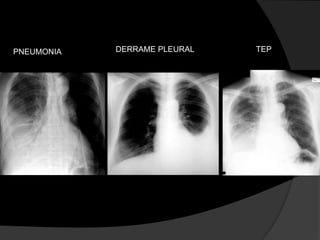

Avaliação InicialOutras condições clínicas podem produzir imagens radiológicas semelhantes ao derrame pleural, de forma que estudos alternativos são frequentemente necessários para confirmar se um derrame pleural está presente.

DERRAME PLEURALTEPPNEUMONIA

Avaliação InicialOutras condiçõesclínicas podem produzir imagens radiológicas semelhantes ao derrame pleural, de forma que estudos alternativos são frequentemente necessários para confirmar se um derrame pleural está presente.